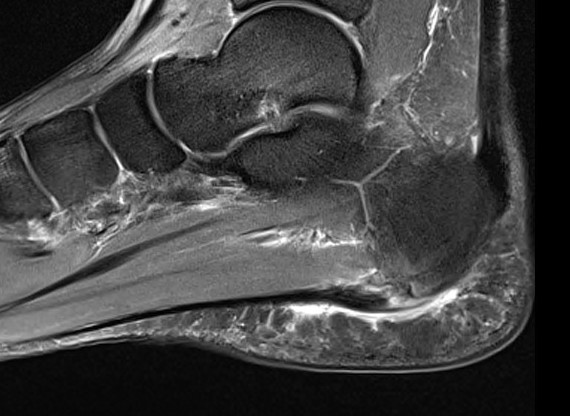

MRI

Thickened plantar fascia with tears

Exclude - retrocalcaneal bursitis / calcaneal stress fracture / Baxter's neuroma / tarsal tunnel syndrome